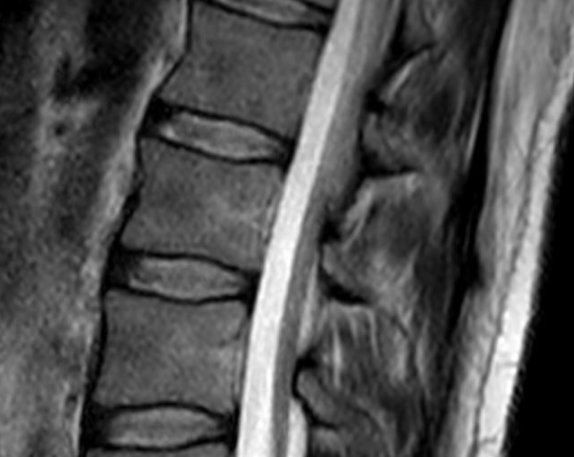

**MRI**는 자기장과 전파를 이용해 인체 내부를 매우 정밀하게 촬영하는 검사입니다.

✔ 실제 사용 사례

- 허리디스크 진단

- 뇌종양 검사

- 무릎 인대 파열

- 척추 신경 압박 확인